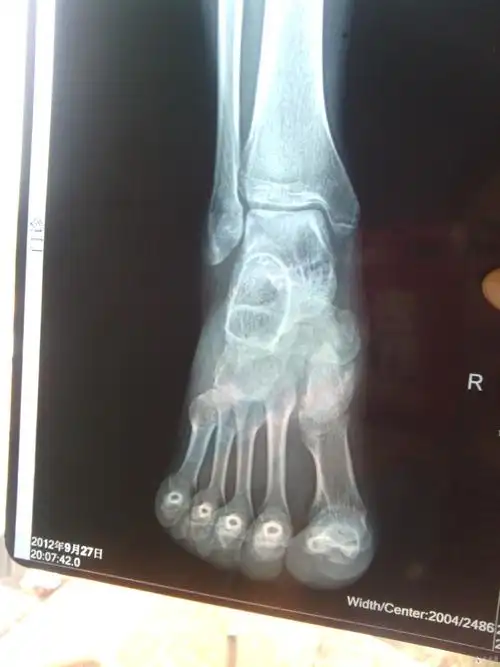

胫骨内侧髁骨折

右脚内踝骨折,有uu帮忙看看这个伤的严重吗